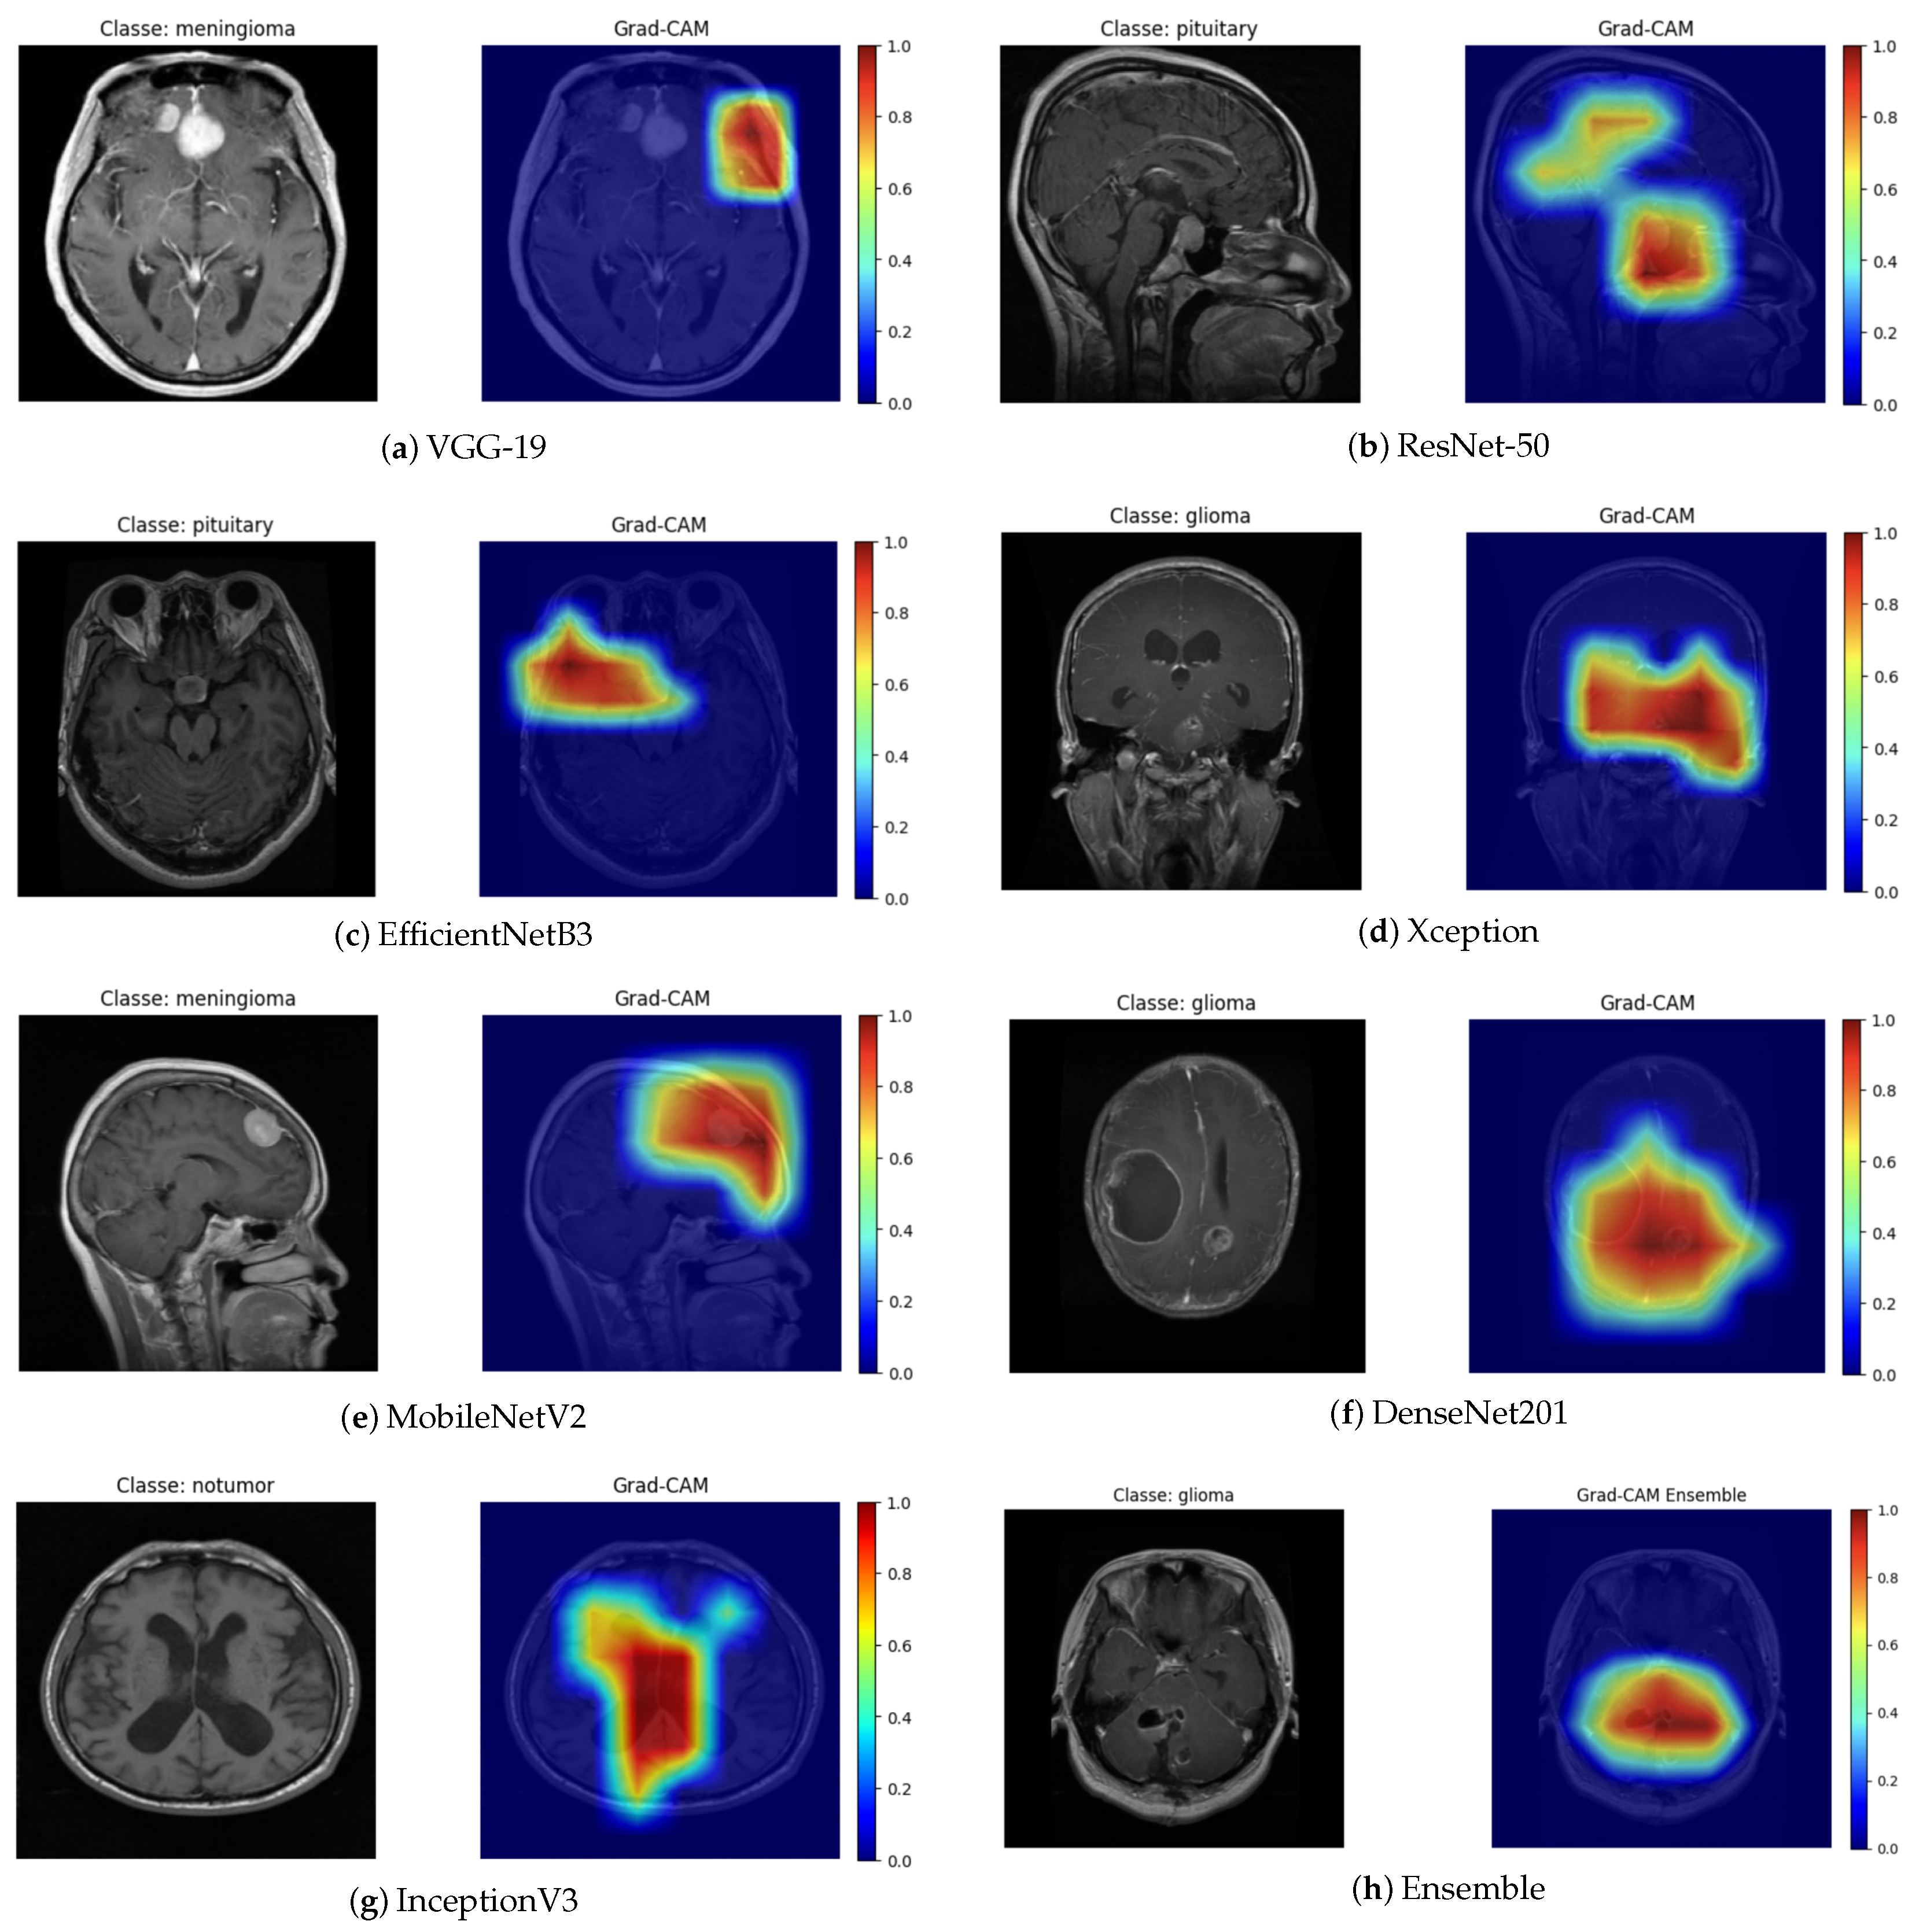

The Grad-CAM technique generates activation maps that highlight the regions of the image that contributed the most to the final prediction. By analyzing the heat maps (Figure 8), it can be observed that the models mainly focus their attention on the anatomical regions corresponding to the brain tumor. The areas highlighted in red indicate higher relevance in the decision-making process, suggesting that neural networks effectively focus on clinically significant regions. This characteristic is particularly important, as it ensures that predictions are not based on noise or irrelevant image artifacts.

Figure 8.

Grad-CAM visualization for different architectures.

The Grad-CAM maps highlight regions that the models consider most important for classification. In most cases, these regions correspond to the approximate location of the tumor, capturing the general area where abnormal tissue is present. For example, in the VGG-19 and MobileNetV2 outputs, the highlighted areas roughly align with the visible tumor mass in the original MRI slice. The DenseNet201 and Ensemble maps also show activations concentrated in the central or upper portions of the tumor, consistent with the lesion’s main location. Overall, the Grad-CAM maps provide a qualitative understanding of model focus, showing that the networks largely attend to tumor regions, though some false positives are present. This emphasizes the need for careful clinical interpretation and potential integration with more precise segmentation methods for clinical use.